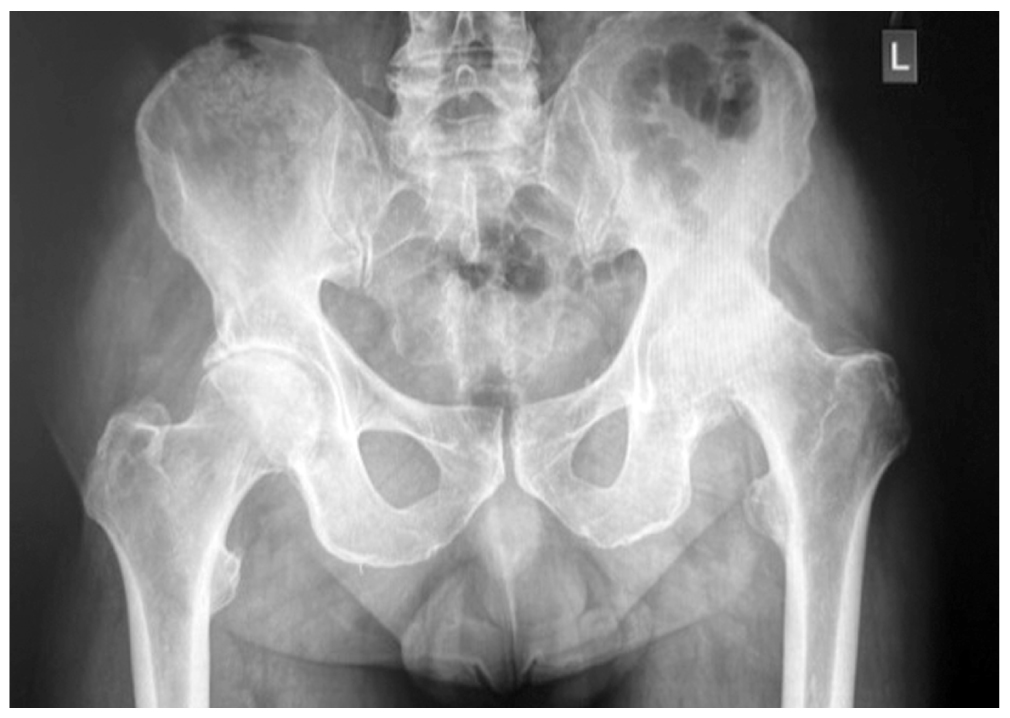

Двусторонний коксартроз слева IV стадии, справа III стадии; асептический некроз головки левого бедра (по классификации Kellgren и Lawrence); рис. 1.

Рис. 1. Рентгенограмма тазобедренных суставов. / Fig. 1. Radiography of the hip joints.